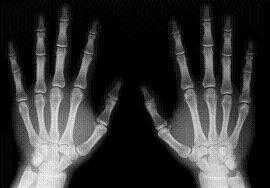

P3: Baules (projectes) Feu un comentari / I3 Informació Setmanal Portada / Per admin Us tornem a demanar un altre cop la vostra col·laboració per tal de treballar la nostra primera baula (projecte) sobre els cocodrils i els pingüins. Necessitaríem radiografies d’alguna part del cos i ecografies de nadons. Moltes gràcies. Mestres de P3